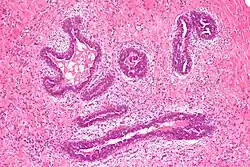

Early histological features expected to be seen on examination of gynecomastic tissue attained by fine-needle aspiration biopsy include the following: proliferation and lengthening of the ducts, an increase in connective tissue, an increase in inflammation, and swelling surrounding the ducts, and an increase in fibroblasts in the connective tissue.[26] Chronic gynecomastia may show different histological features such as increased connective tissue fibrosis, an increase in the number of ducts, less inflammation than in the acute stage of gynecomastia, increased subareolar fat, and hyalinization of the stroma.[24][26] When surgery is performed, the gland is routinely sent to the lab to confirm the presence of gynecomastia and to check for tumors under a microscope. The utility of pathologic examination of breast tissue removed from male adolescent gynecomastia patients has recently been questioned due to the rarity of breast cancer in this population.[57]